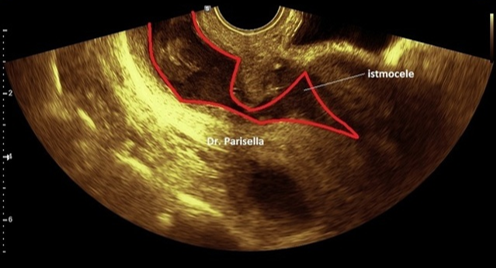

Но клинические проявления не отражают действительной тяжести состояния пациентки, поэтому решающее значение при диагностике имеет обследование с проведением трансвагинального УЗИ, гидросонографии, гистероскопии, МРТ органов малого таза. У 70% пациенток в зоне рубца определяется наличие ниши — дефекта стенки со стороны полости матки, имеющей вид неправильной конусовидной формы с выраженным истончением в дистальной зоне. Этот признак частичного расхождения шва на матке практически невозможно обнаружить клинически.

У трети пациенток толщина миометрия составляет 1,5-2,5 мм, появляются локальные изменения его структуры в зоне рубца или диффузные — в виде множественных очагов пониженной эхогенности с нечеткими контурами, расположенные в передней стенке матки. Также в зоне рубца может определяться эндометриоидный инфильтрат, который требует оперативного удаления. Оценка состояния рубцовой ткани с помощью диагностических методик позволяет судить об особенностях рубца еще до наступления повторной беременности, что важно для прогноза предстоящих родов.